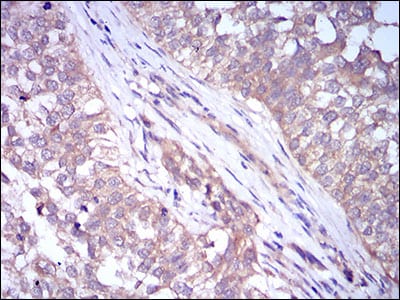

Immunohistochemical analysis of paraffin-embedded human bladder cancer tissues using PLIN2 mouse mAb with DAB staining.